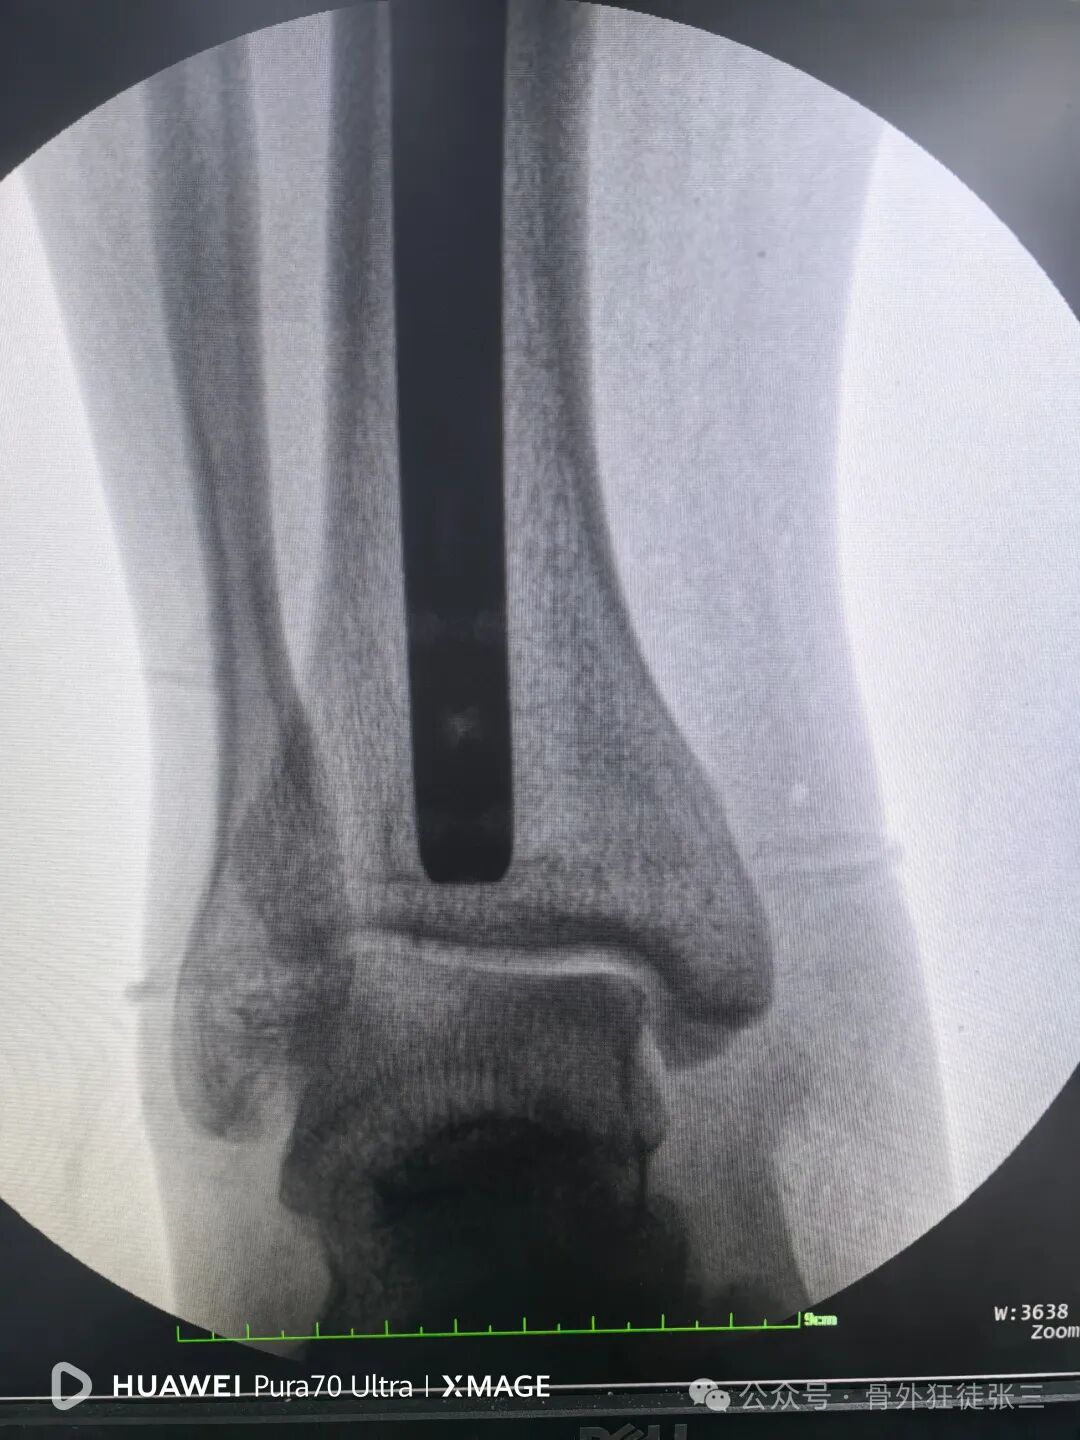

远端安装瞄准架

骨折间隙顺利缩小

锁近端两枚锁钉

尾帽顺利锁定